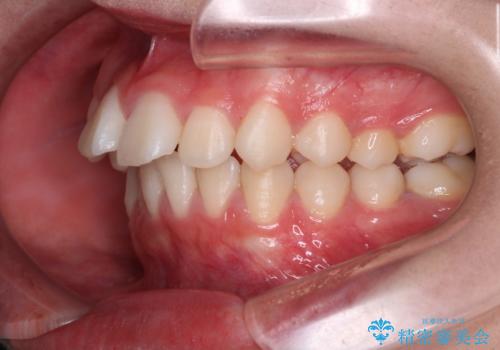

- 前歯の叢生と突出感を主訴に来院されました。

抜歯をしてワイヤー矯正を行いました。

上顎両側小臼歯を抜歯して治療を行い、突出感も大幅に改善しました。